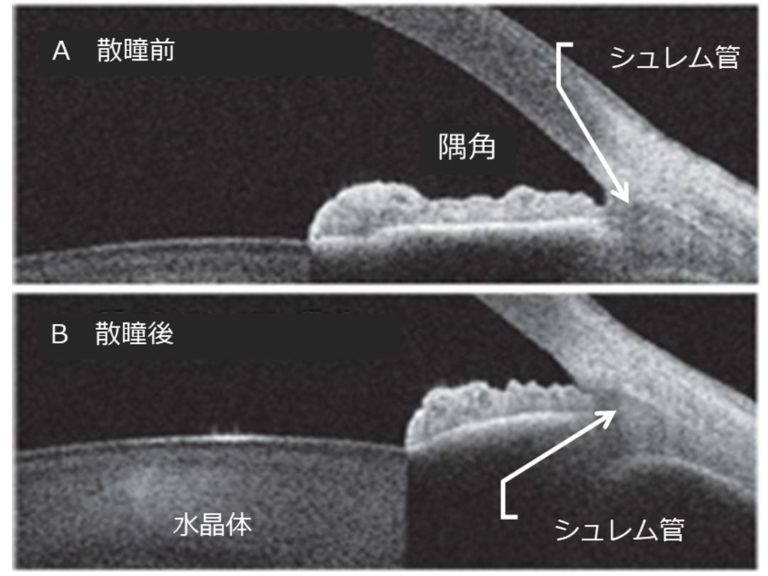

閉塞隅角緑内障の場合、眼から液体が正常に流れ出ないため、圧力が高まります。

液体は、虹彩の後ろの眼の後房で生成されます。この液体は通常、瞳孔を通って眼球の前房に流れ込みます。

次に、液体は小柱網と呼ばれる一連のチャネルを通って、強膜 (白目) の静脈に流れ込みます。

閉塞隅角緑内障では、小柱網が閉塞または損傷します。液体はこの排水経路を容易に通過できないか、完全にブロックされています。この液体のバックアップにより、眼球内の圧力が上昇します。